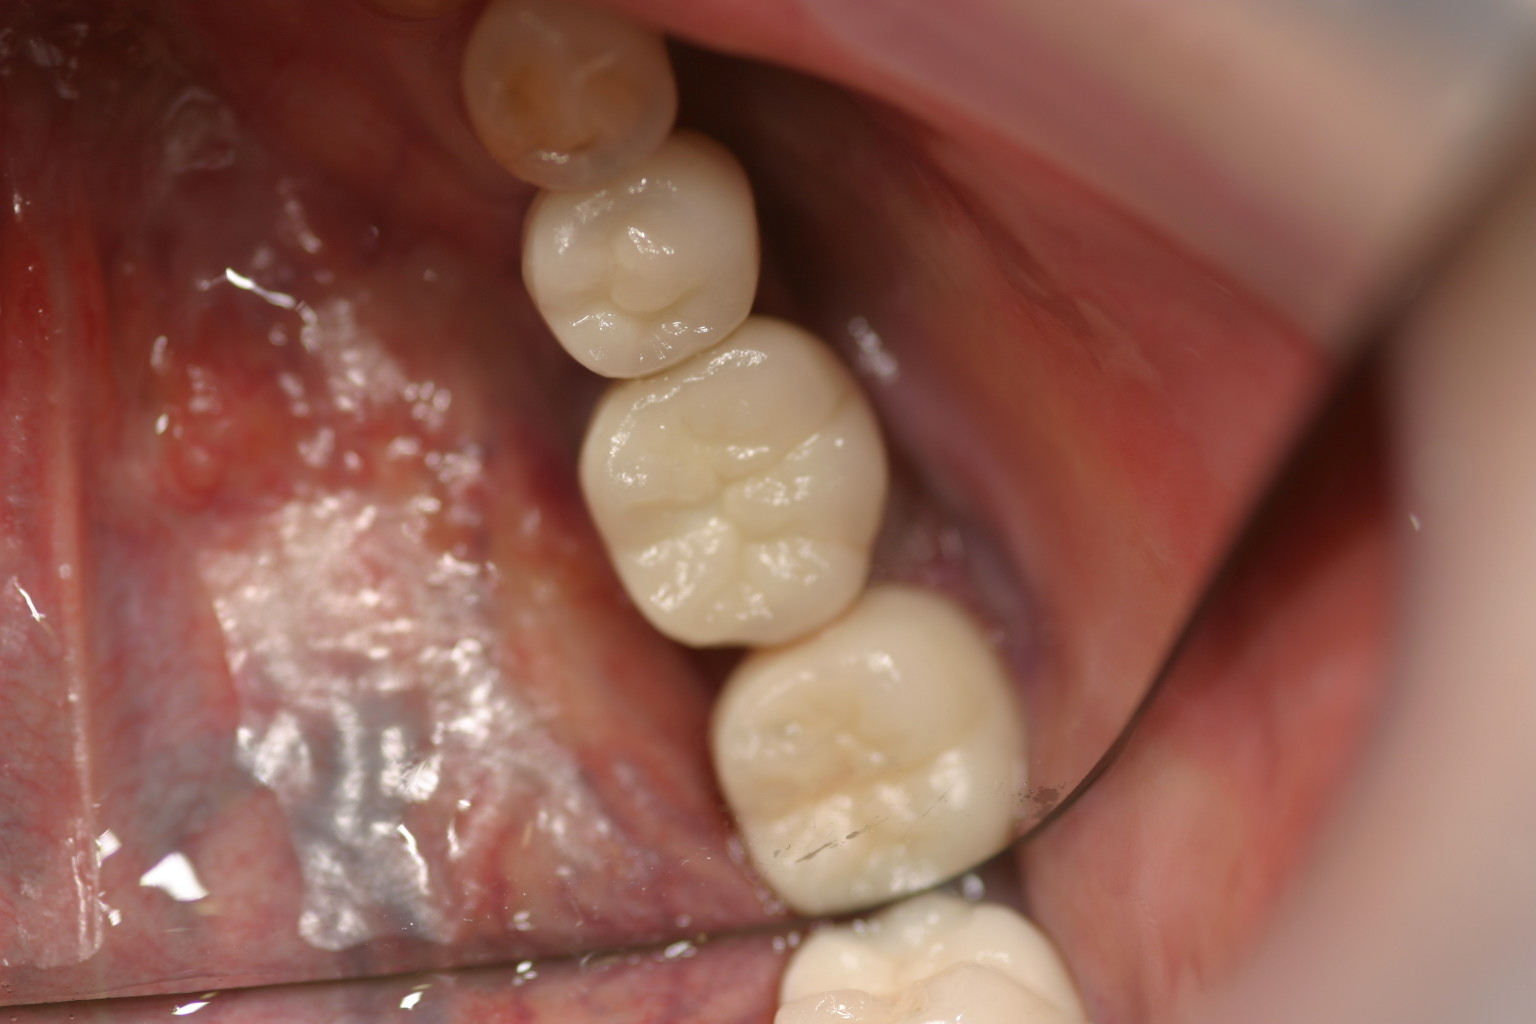

左下567番インプラントジルコニアアバットメント及びジルコニアセラミッククラウン装着